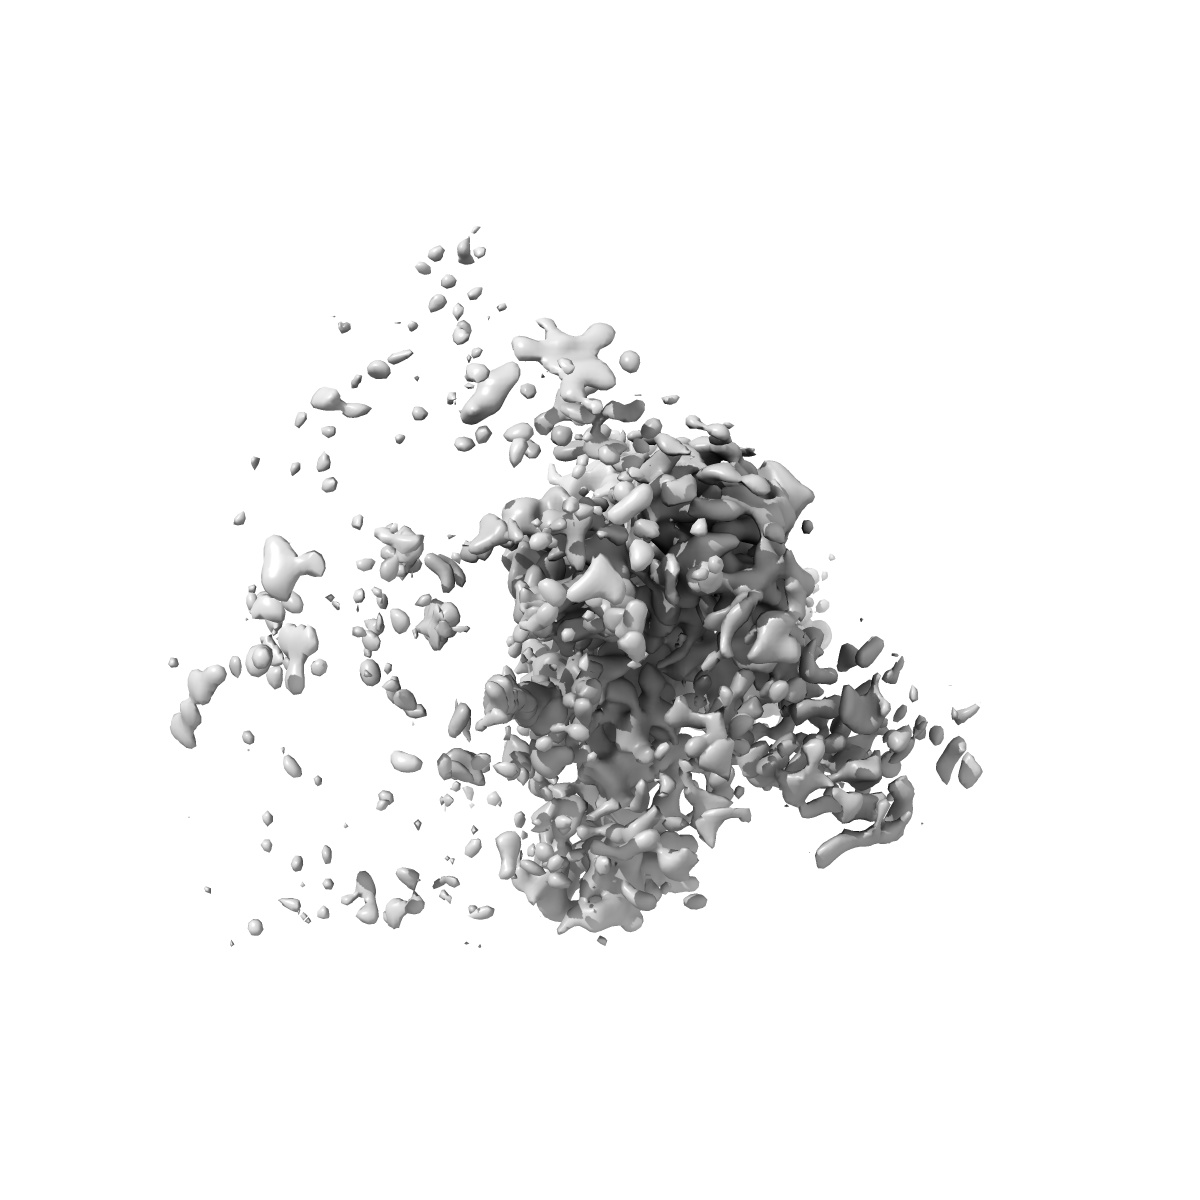

Cryo-EM structure of SARS-CoV-2 BA.4/5 spike protein in complex with 1G11 (local refinement)

Single-particle3.98 Å

Sample: SARS-CoV-2 BA.4/5 spike protein in complex with 1G11